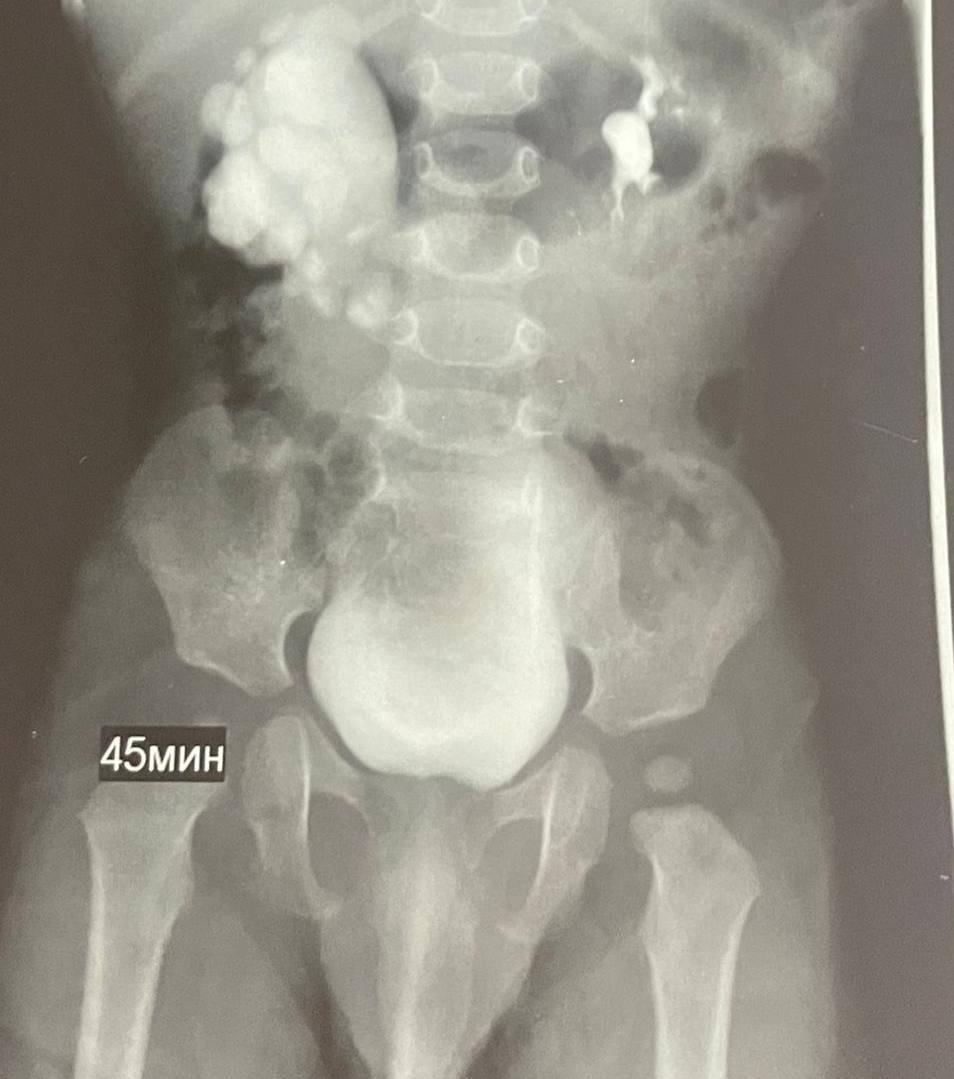

У ребёнка ещё до рождения заметили проблемы с почкой на УЗИ, а после появления на свет состояние стало ухудшаться — диагностировали гидронефроз. При этом опасном состоянии почка могла бы перестать функционировать.

В ноябре врачи ставропольской больницы скорой помощи провели малышу необходимую операцию: удалили суженный участок мочеточника, создали новое соединение и восстановили нормальный отток мочи. Так врачи сохранили ребенку правую почку.